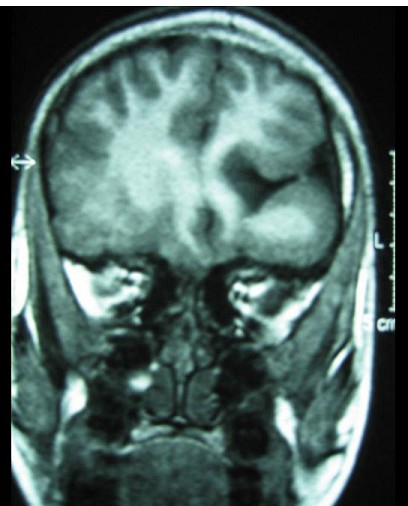

9岁男孩,有癫痫发作史,MR表现如图,首先考虑以下哪个疾病 ( ) TLC-00501.jpg TLC-00502.jpg TLC-00503.jpg TLC-00504.jpg

• A.胼胝体发育不全

• B.脑灰质异位

• C.Dandy-Walker综合征

• D.脑裂畸形

• E.无脑回畸形